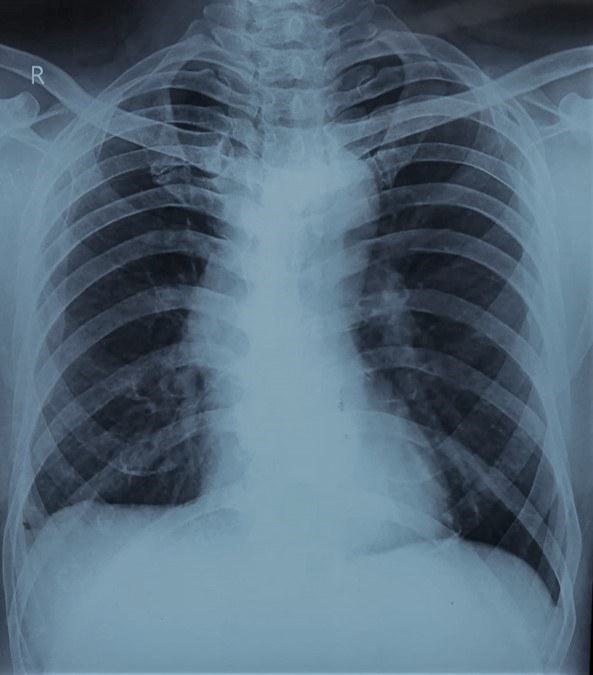

A 39-year-old, man presented to the chest clinic with complaints of right-sided chest pain and mild exertional dyspnea for the last six months. The pain was dull aching in nature and localized to the right lower axillary area and back. There was no history of fever, weight loss or loss of appetite. He had completed six months of anti-tubercular therapy (Rifampicin, isoniazid, ethambutol and pyrazinamide) on a clinical-radiological basis for right-sided pleural effusion one year back. On physical examination his heart rate was 84/min, respiratory rate was 16/min, saturation was 98% at room air by pulse oximetry and blood pressure 134/80 mm of Hg. The respiratory system examination revealed decreased vesicular breath sounds in the right infra-axillary and infra-scapular areas. All the routine blood investigations including haemogram, liver profile and renal profile were within normal limits. His chest radiograph showed blunting of the right costophrenic angle (figure 1). The B mode ultrasonographic image of the right lower chest wall alone and with the colour Doppler is shown in figure 2.